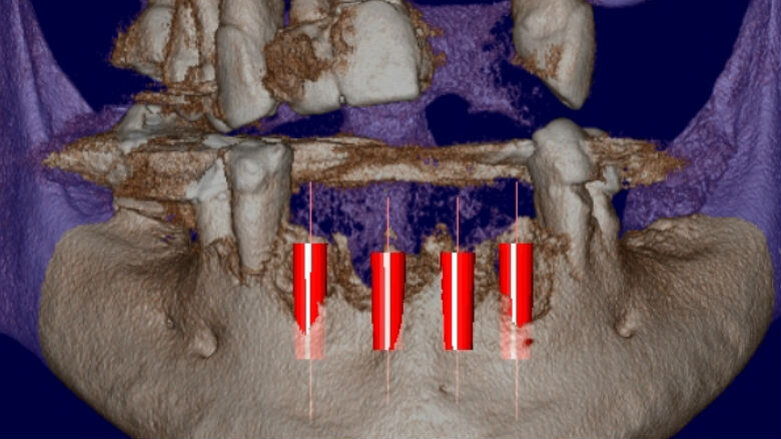

Viene presentato il caso di un paziente (maschio, 57 anni) inquadrato nosologicamente come ASA 1 e riferito alla nostra osservazione per la riabilitazione implantoprotesica di un’area edentula in mandibola anteriore (Fig. 1). Le indagini radiografiche di 1° e 2° livello (ortopantomografia e CBCT) evidenziano una marcata atrofia ossea di tipo combinato (classificabile come grado 3 sec. Seibert) che controindica l’inserimento di impianti osteointegrati (Fig. 2). Considerato il notevole riassorbimento della cresta ossea, per ridurre il rischio di incidenti intraoperatori e poter pianificare al meglio l’intervento chirurgico, viene simulato il posizionamento di 4 impianti Resista IA3413 (Resista, Via F.lli Di Dio, 68 – Omegna, VCO) tramite il software per ricostruzione tridimensionale Real Guide Ver. 5.0 (3Diemme, Como).

Gli impianti vengono presi dalla libreria Resista presente sul software Real Guide Ver. 5.0 (3Diemme, Como) e posizionati con la corretta angolazione e profondità nella cresta atrofica da riabilitare: la ricostruzione tridimensionale prevede una parziale esposizione delle fixtures (Figg. 3, 4). In base ai dati assunti dalla simulazione, viene quindi programmato un intervento di Rigenerazione Ossea Guidata (G.B.R.) con membrane di tipo non riassorbibile in PTFE associata a un innesto di tipo composito (costituito da particolato osseo autologo in chips miscelato a un biomateriale di origine eterologa) e al contemporaneo inserimento di 4 impianti osteointegrati. La profilassi antibiotica è iniziata un’ora prima dell’intervento (amoxicillina/acido clavulanico, Augmentin, Glaxo-SmithKline, Verona, Italia, 2 g 1 ora prima della chirurgia e poi 1 g ogni 12 ore per 6 giorni).

Fig. 4 - Simulazione preimplantare che evidenzia la limitata disponibilità ossea in senso verticale e orizzontale.